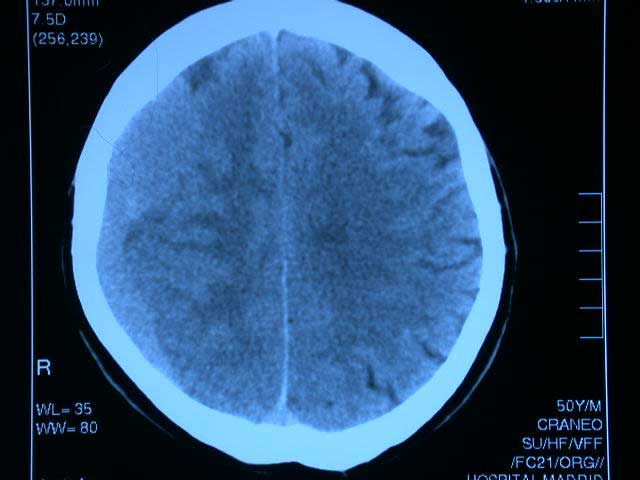

El uso creciente de fármacos anticoagulantes y antiagregantes se asocia a un aumento de hematomas subdurales, especialmente en los mayores de 75 años. La combinación de antagonistas de vitamina K con antiplaquetarios potencia el riesgo. JAMA, 28 de febrero de 2017